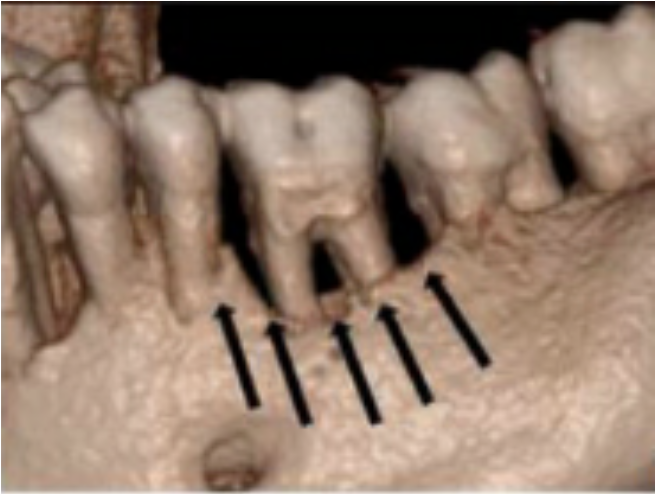

Der kan også komme gentagne smertefulde infektioner omkring dem. Det sker særligt når knoglen er forsvundet mellem rødderne på de bagerste kindtænder. Det er sket for den midterste tand på billedet til venstre. Denne tand er nu svær at behandle, fordi sygdommen er fremskreden.

På et tidspunkt når parodontosen ind mellem rødderne på de bagerste kindtænder. Nu er det meget sværere at behandle sygdommen Nogle steder løber processen hurtigere, så der dannes dyb smalle sprækker ned i knoglen som er fyldte med bakterier, men vanskelige at rense ned i. Dette vanskeliggør også behandlingen. Det er fra der af, at tænder må fjernes.